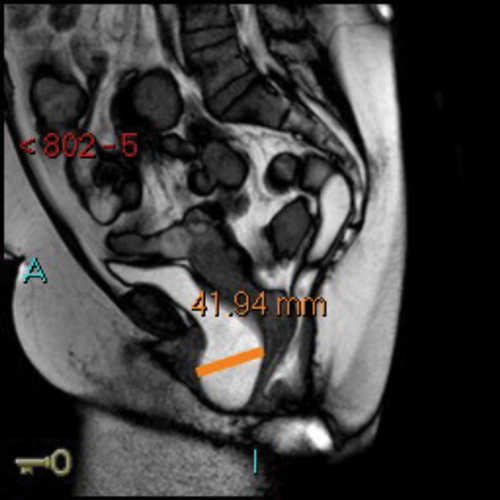

MR defecating proctograms are performed in a 1.5 Tesla MR scanner (Philips Sense). A similar detailed explanation of the procedure and consenting process takes place, so the patient knows what to expect during the three ‘cine’ scans of ‘squeeze up’, ‘bear down’ and ‘empty out’. The urinary bladder must be empty as far as possible during the MR scan.

After an initial digital rectal examination, 120mls of ultrasound jelly is instilled into the rectum via a rectal tube with the patient in the left lateral position. The patient is then turned to lie supine and positioned so that the top of the Sense-body coil is at same level with the iliac crest. The MRI scan protocol includes T2 axial and coronal sequences and sagittal ‘cines’ squeeze, bear down and two defecatory attempts with a couple of minutes rest in between. In cases of incomplete evacuation, a repeat evacuation may be needed or a coronal cine.

In addition the anterior and middle compartment is assessed, particularly for the presence and anatomy of a cystocoele or vault prolapse. The T2 sequences also allow pelvic evaluation for other incidental pathologies (Figure 2).

Figure 2a: Baseline MR proctogram.

Figure 2b: Pelvic floor descent MR proctogram.

Figure 2c: Large cystocoele MR proctogram.

Figure 2d: Large rectocoele on MR proctogram.